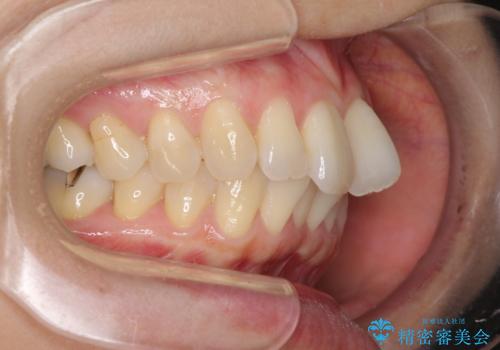

上顎前歯の叢生が解消されると出っ歯になることが分かっていたので、両側奥歯付近にアンカースクリューを入れ、出っ歯を改善するためのゴムかけを行いました。

ゴムかけを頑張っていただいたので、当初の予定通り、1年強で治療を終えることができました。